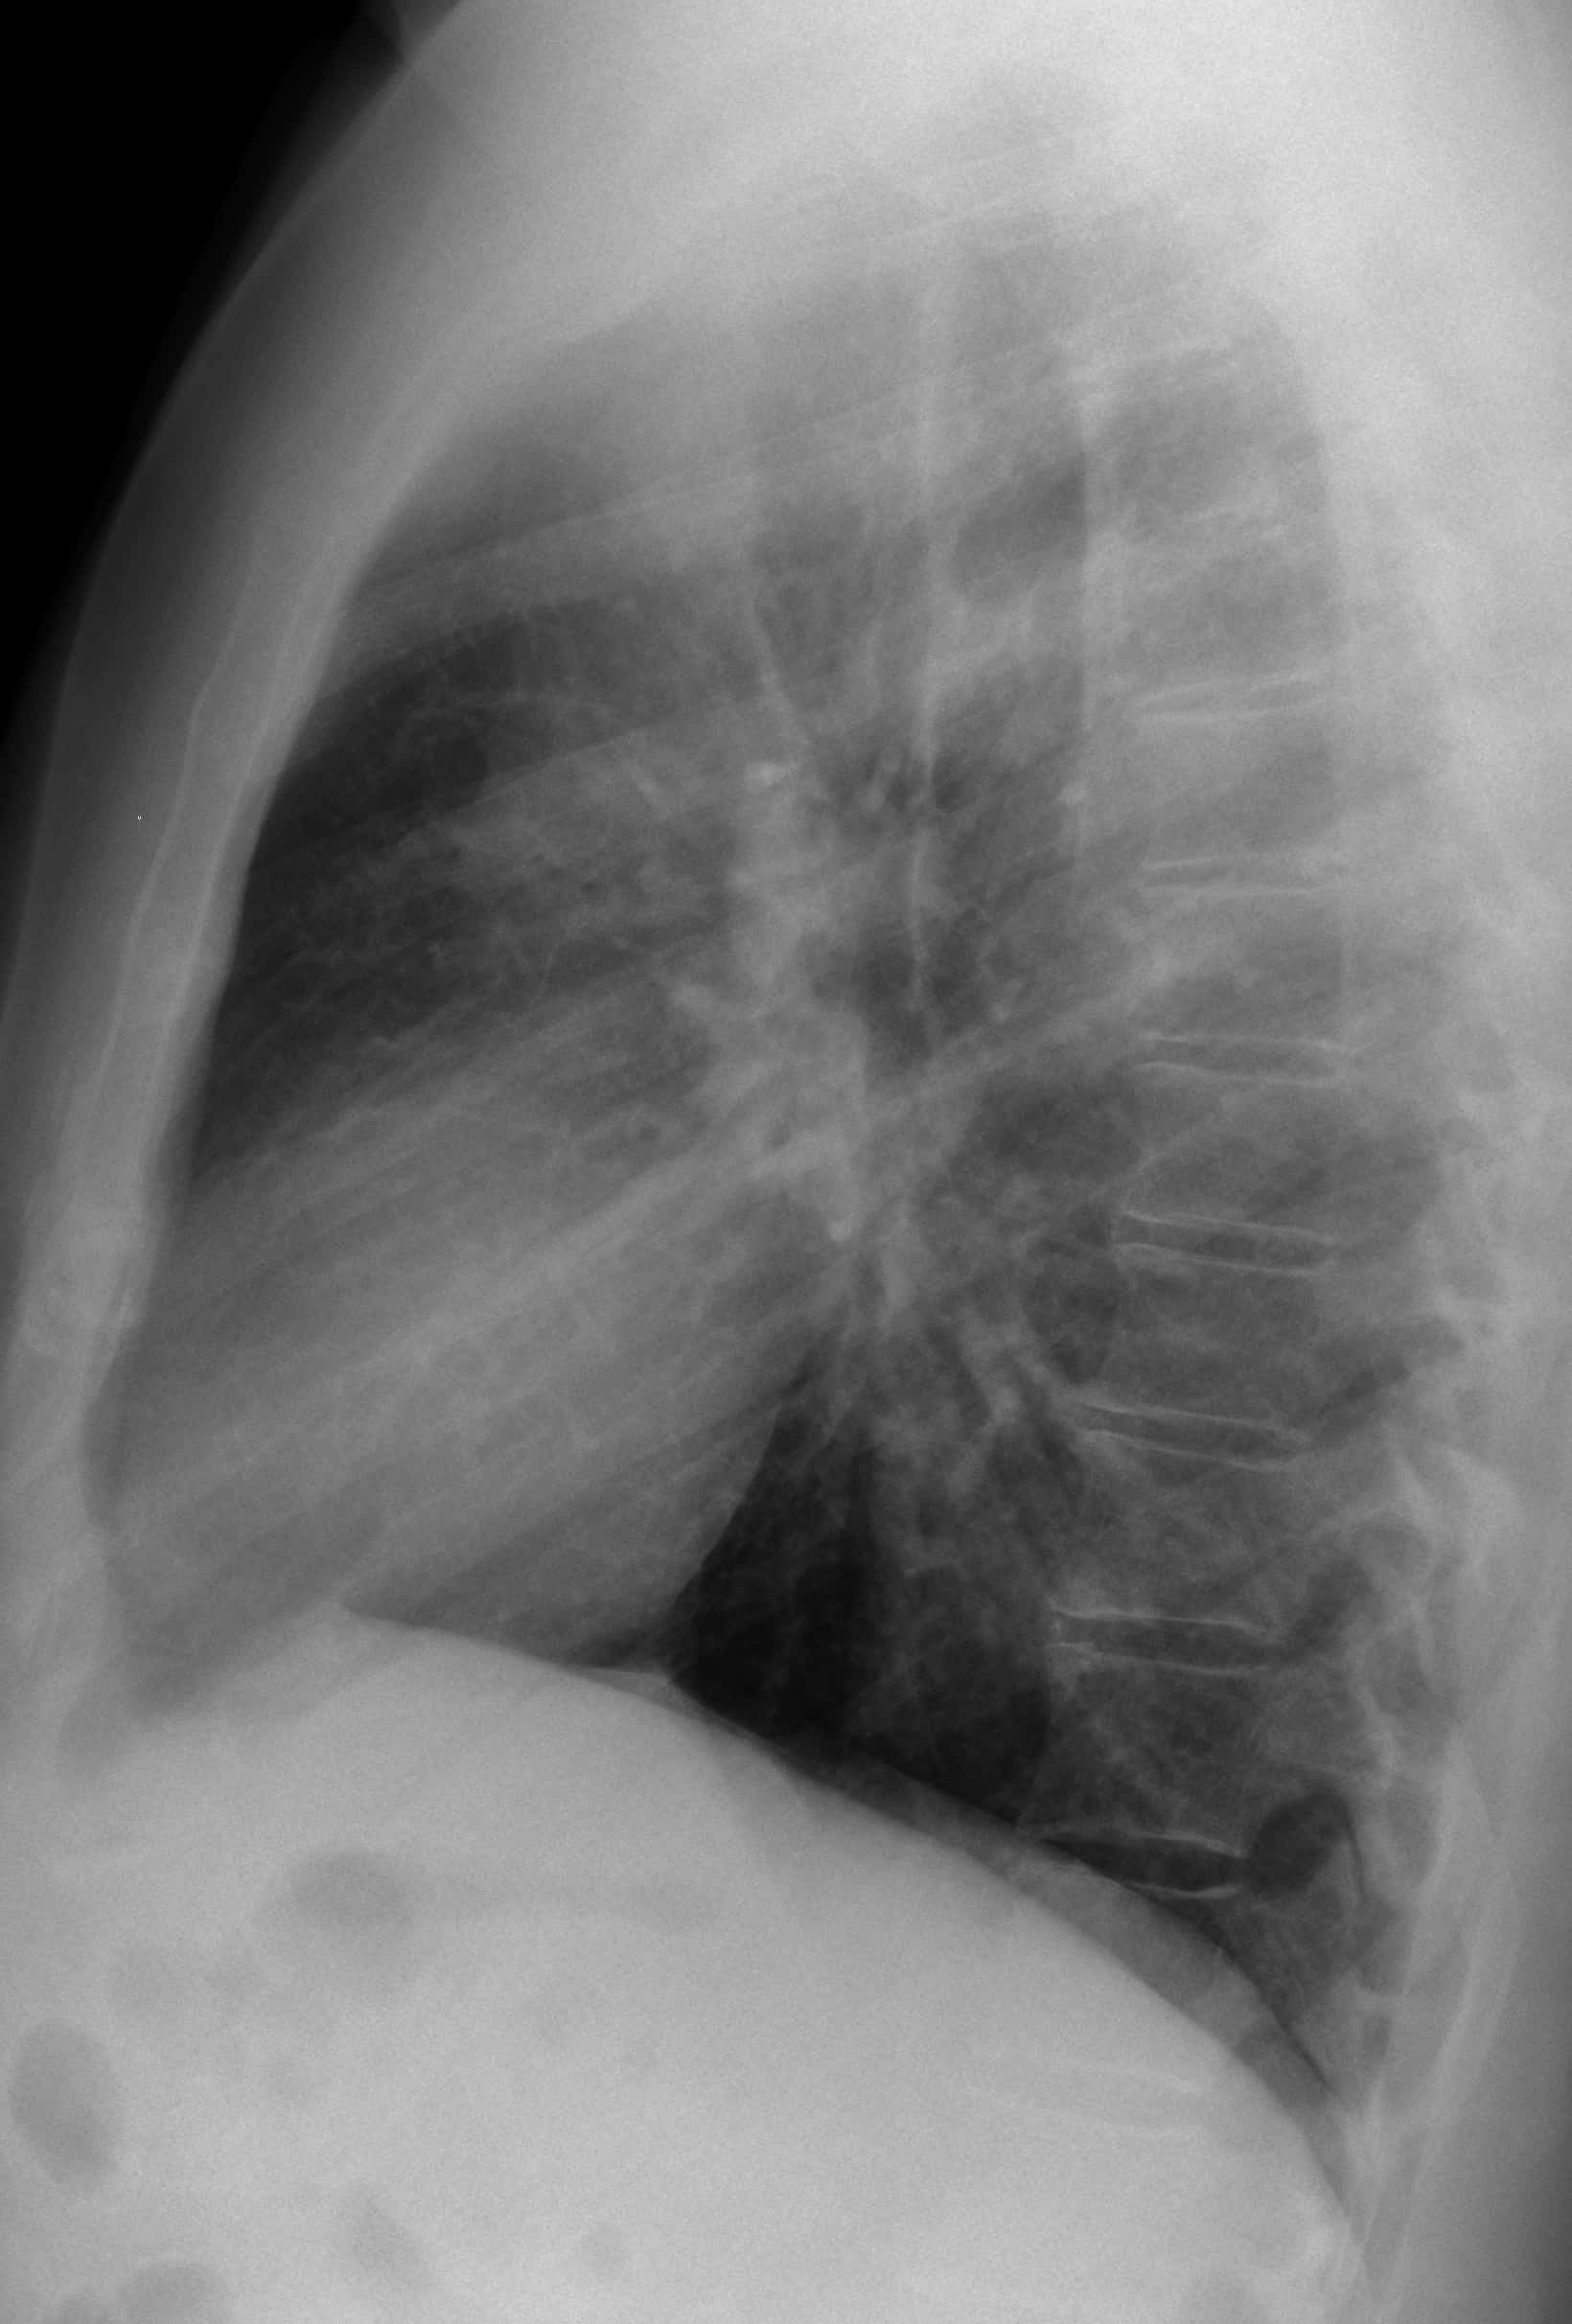

Phình ĐM chủ - Ảnh 4

Phình ĐM chủ

» Thông tin: Nam giới – 45 tuổi.

» Lâm sàng: Đau ngực.